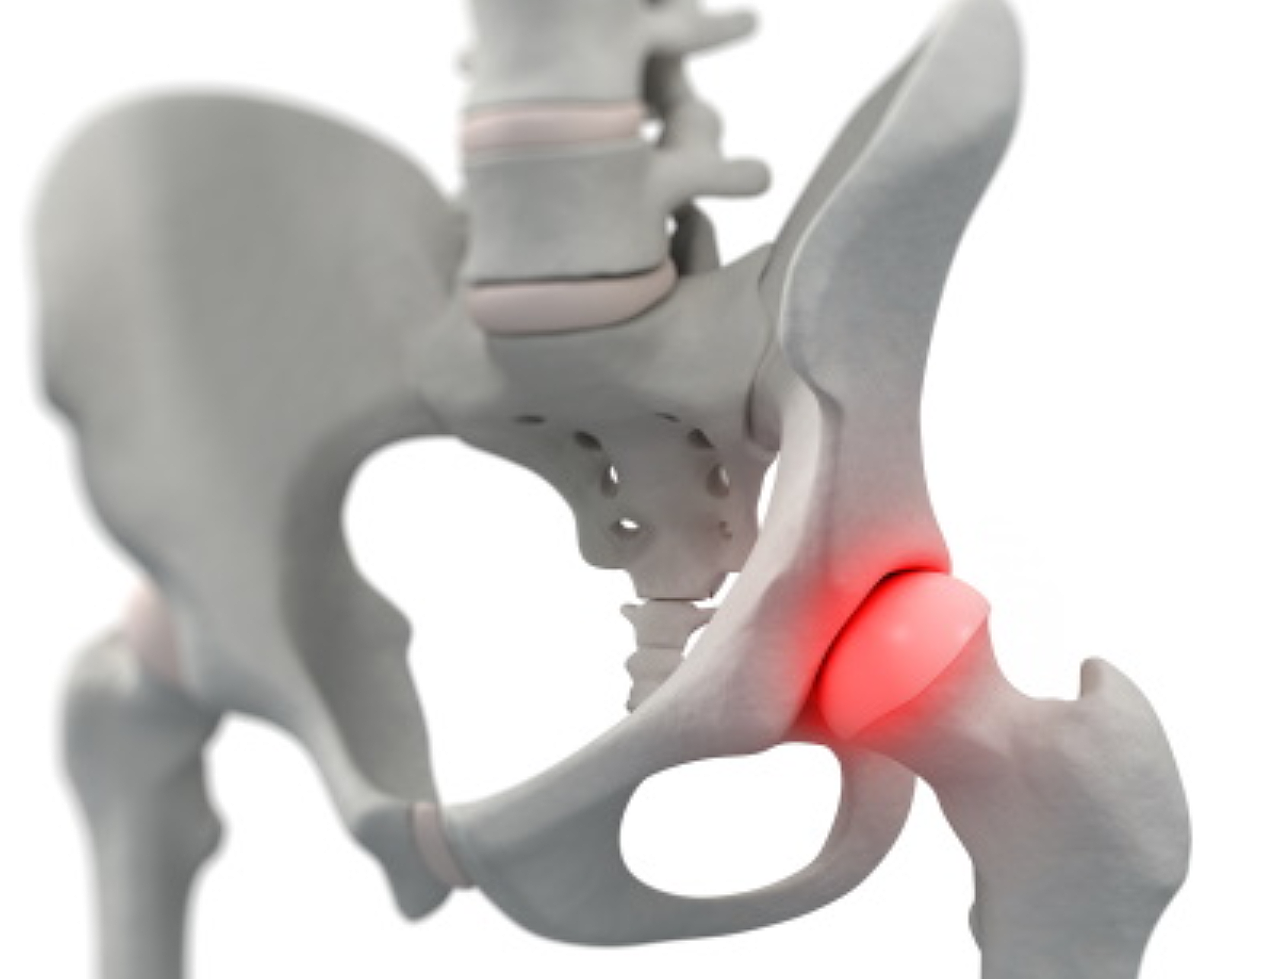

고관절 통증 증상(엉덩관절)은 오른쪽과 왼쪽의 골반과 넙다리뼈가 연결된 관절의 통증을 얘기합니다.고관절은 상체의 하중을 분산시키는 역할을 하며, 걷는 동안 체중의 3배, 달리는 경우 10배에 가까운 하중을 받습니다. 다른 관절과 마찬가지로 감당하기 어려운 충격이나 무게가 가해지면 고관절 통증 증상이 발생합니다. 퇴행성 고관절염, 대퇴골 골절, 대퇴골두 무혈성 괴사, 선천성 고관절 탈구 등이 대표적인 고관절 통증 질환입니다.

고관절은 골반 뼈 속에 공처럼 생긴 대퇴골의 골두가 맞물린 관절입니다. 대퇴골두는 다른 부위에 비해 혈액 순환 장애가 쉽게 올 수 있으며, 혈액 순환 장애는 대퇴골두 무혈성 괴사를 유발합니다. 뼈가 썩으면 몸의 하중을 정상적으로 견디지 못해 미세구조에 골절이 생기고, 심각한 통증이 발생합니다.